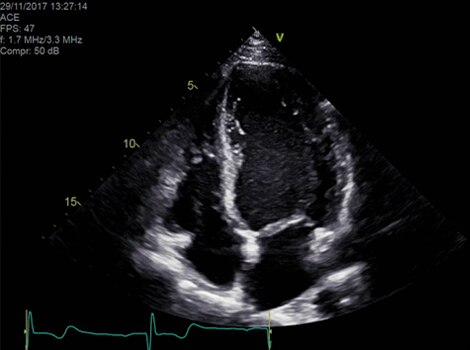

Vivid Portfolio

Cardiac Auto Doppler automatically provides Doppler measurement results for the most common parameters, with minimal user guidance.  Read More

Vivid E95

cSound™ beamforming technology for exceptional visualization quality with impressive resolution in 2D, color flow, Doppler and 4D formats. Read More